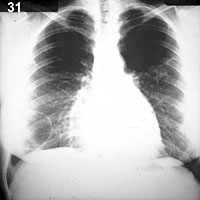

ESQUEMA 31 Comentario placa 31 En la base derecha se ve una imagen anular de unos 6 cm. de diámetro, de pared muy fina y con contenido aéreo. Lo mas probable es que se trate de un quiste o de una bula, pero son necesarios más antecedentes clínicos y exámenes para identificar su origen. Pase a la placa 32 y resalte las diferencias con la recién vista |